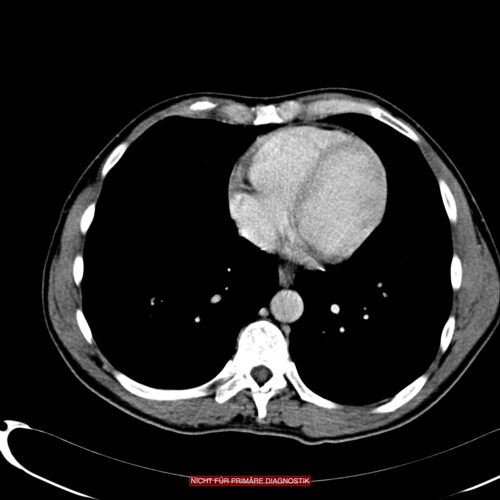

Bei Vorliegen eins Strangulationsileus ist eine Notfall-Operation indiziert. Der mechanische Ileus ohne Gefäßbeteiligung muss in aller Regel ebenfalls operiert werden, allerdings nicht mit derselben Dringlichkeit. Lässt sich in der CT-Untersuchung mit oraler Kontrastmittelgabe ein Kalibersprung im Dünndarm nachweisen, ist die Wahrscheinlichkeit gering, dass es ohne eine Operation zu einer Besserung kommt.Ein Verschluss des Dickdarms kann längere Zeit asymptomatisch bleiben, während ein hoher Dünndarmileus bereits frühzeitig zu Erbrechen führen wird. Das typische Zeichen eines Ileus ist Stuhlerbrechen, also Miserere sowie metallisch klingende, hochgestellte Darmgeräusche.